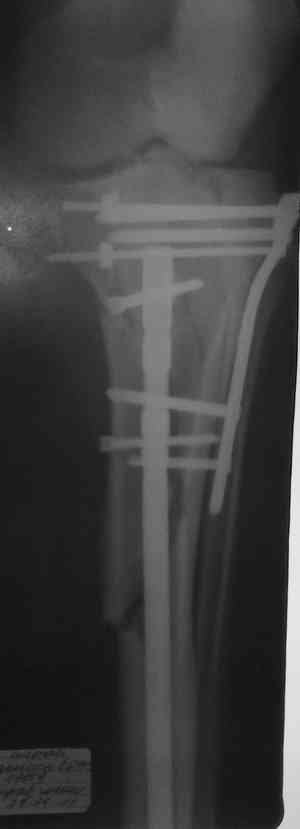

Решили выполнить остеосинтез штифтом и внутрисуставного перелома пластиной и винтами. Жду мнения! Зачем мне оправдываться-я же не преступник. Диалогом называется...

Отдельные переломы тибиал плато и перелом проксимальной трети большеберцовой кости отличаются от переломов тибиал плато с вовлечением диафиза. Здесь перелом тибиал плато типа Schatzker VI, полученный в результате высокоэнергетической травмы. Перелом метафиза образовал отрыв суставной поверхности от диафиза с вовлечением медиального и латерального мыщелков. Двухмыщелковые переломы из-за укрочения опасны развитием компартаментального синдрома, повреждением латерального мениска и связок.

При переломах одного из мыщелков тибиал плато+дополнительный перелом проксимальной трети большеберцовой кости можно применить комбинированный вариант фиксации, т.е. мыщелок винтами или пластиной, а для диафиза можно установить гвоздь. В данном варианте потеряно преимущество гвоздя , из-за серьезной травмы суставной поверхности нельзя нагружать ногу несколько месяцев. А без нагрузки гвоздь просто заполнитель пространства внутри кости!

На вашем место я бы подождал с фиксацией до готовности кожных покровов, и за это время можно было подобрать соответствующий фиксатор, т.е более длинная пластина снаружи и медиальная пластина на апексе перелома как подпорка. Здесь приемлем как раз минимальный доступ.

Имеющаяся импрессия не потребовала пластики - достаточным оказалось поднять отломок

Если там действительная импрессия, пустое место без структуральных заполнителей, кость или синтетические материалы, не восстановится, а образуется коллапс, и ось конечности поведет после нагрузки. Кроме того там возможно "болт стяжка"?, в медиальной стороне выступает за кортекс, можно было укоротить! Потом создается впечатление, что не соответствуют мыщелки большеберцовой и бедренной костей? Покажите снимок.

Ваша упорство с минимальными данными защищаться забавляет, и пока не все убедились в Вашей правоте. Для нормальной защиты необходимы аргументированные доказательства исследованиями. КТ сканы и прицельно сделанные снимки коленного сустава, а так все аргументы - не более чем "моя фиксация, мне нравится". Без этих доказательств пока только Ваше упорство.....

Здесь пару случаев для сравнения,...в первых 1-4 слайдах метод фиксации одним фиксатором, как видно после 8 месяцев сохранилась ось. С 5 по 9 вариант двумя пластинами...